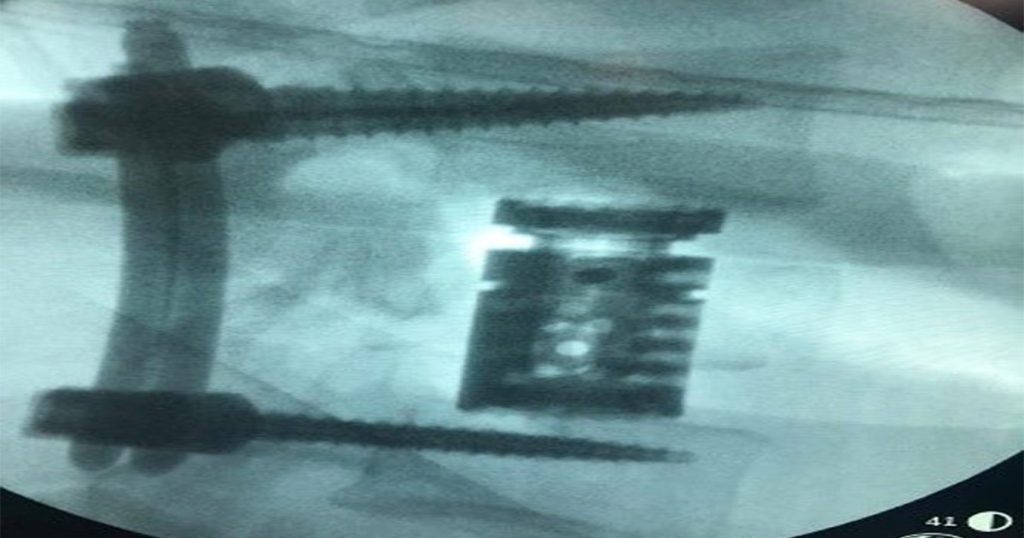

Posteriormente, se hacen imágenes de apoyo diagnóstico para analizar la severidad de los traumas. Sin evidencia de trazos de fracturas, alineación conservada, sin presencia de espondilo listésis; tomografía de cráneo, sin evidencia de trazos de fracturas o hundimientos en bóveda ni en base craneal sin presencia de colecciones intracraneales evacuables, sistema ventricular simétrico, línea media conservada, cisternas peri mesencefálica presente y simétrica. El TAC de columna lumbosacra evidenció fracturas por aplastamiento de cuerpos de L1, L3 (hubo estallido) L4 con compromiso de estabilidad del segmento por lo cual amerita realizar lumbosacra para evaluar compromiso discoligamentario.

Por lo cual a este paciente de 25 años se realiza procedimiento quirúrgico donde la junta médica definió y se autoriza colocación en decúbito lateral N bloque para evitar úlceras por presión. Además, se hace restauración anatómica por distracción intravertebral de L1, fijación transpedicular de L2-L4 percutánea, vertebrectomia de L3 vía anterolateral con colocación de cilindro expandible. Por último, neurocirugía por artrodesis L2-L4 posterior más corpectomia anterior de L3 más restauración anatómica de L1.